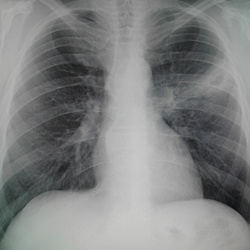

Мужчина 1956 г.р,проф.флг,жалоб со стороны легких не предъявляет,температура нормальная,посмотрела в амб.карте- последняя флг в 2008 году,там была норма,сейчас лечится у невролога по поводу...

Мужчина 1956 г.р.,по первой ФЛГ(в прям.проекц.) писали ему пневмонию слева,сегодня пришел на контрольный снимок-полость на фоне инфильтрации((так,что же это все-таки-такая отрицательная...